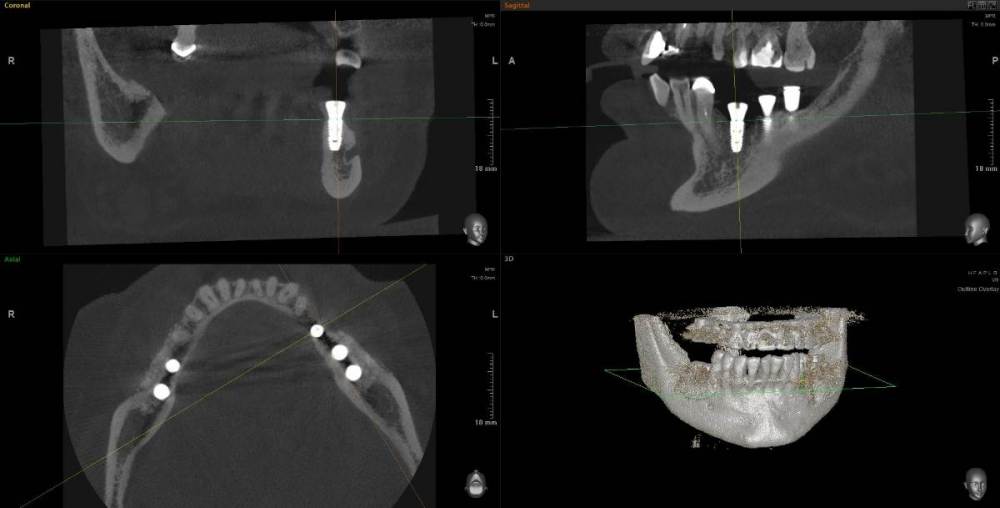

Kostoprav Опубликовано 11 мая, 2021 Поделиться Опубликовано 11 мая, 2021 (изменено) 70%ауто+30% ксено, мембрана цитофлекс, винты самосверлящие после пластики до установки имплантов прошло 8 мес. Изменено 11 мая, 2021 пользователем Kostoprav 3 6 Ссылка на комментарий

Карен Аванесов Опубликовано 12 мая, 2021 Поделиться Опубликовано 12 мая, 2021 20 часов назад, Kostoprav сказал: 70%ауто+30% ксено, мембрана цитофлекс, винты самосверлящие после пластики до установки имплантов прошло 8 мес. Замечательно! 1 Ссылка на комментарий